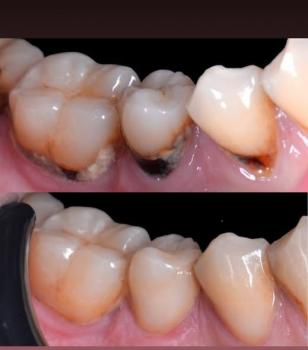

Severity:

Teeth Problems: